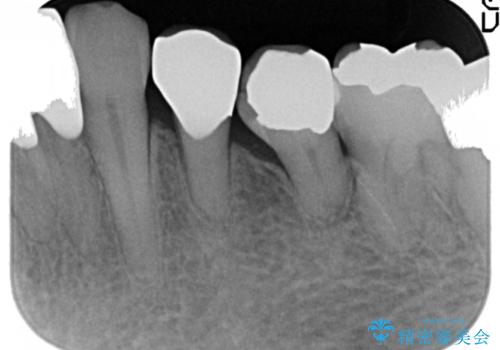

4年前に行った他の部位の治療にご満足頂け、再来院して下さいました。(こちらの症例です→ https://seimitsushinbi.jp/case/68066/ )

以前行った奥歯の治療により下顎前歯の動揺は改善傾向にあり顕著ではなかったのですが、欠けて黒くなっていることと少しの動揺が気になるとのことでした。

元気なうちに治療しておきたいという患者様の強いご希望により、下顎前歯の連結補綴と欠けている小臼歯の補綴治療を行いました。

自然な仕上がりに喜んで下さいました。

クラウンを連結することにより気にされていた動揺もなくなり、安心して頂けました。

被せ物の種類:オールセラミッククラウン スタンダード